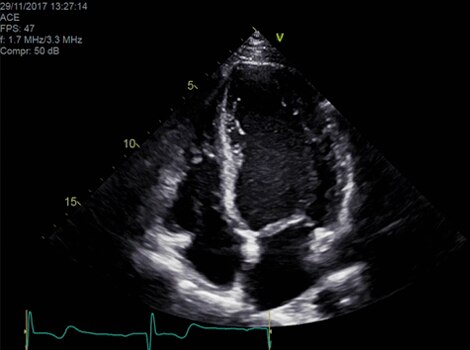

Vivid 产品组合

心脏自动多普勒可自动提供多普勒测量结果,以最小的用户指导获得常见参数。了解更多信息

Vivid E95

cSound™ 波束形成技术可实现卓越的可视化质量,同时在 2D、彩色血流、多普勒和 4D 格式的分辨率令人惊艳。了解更多信息

Vivid S70N 和 Vivid iq IntraCardiac Echo (ICE8,9) E95

ICE 技术联合 CARTOSOUND™ 提供出色的成像细节,加强过程中的实时监控和指导。 了解更多信息

Vivid E95/E90/S70N

cSound™ 波束形成技术可实现卓越的可视化质量,同时在 2D、彩色血流多普勒和 4D 格式的分辨率令人惊艳。 了解更多信息

半自动化定量工具。 了解更多信息